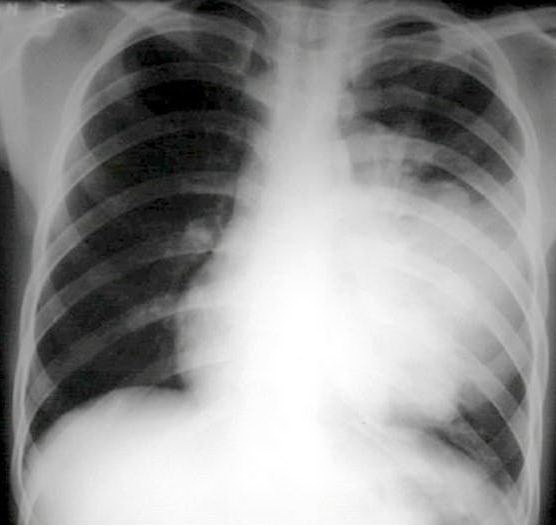

Phế cầu khuẩn là nguyên nhân thường gặp gây viêm phổi và một số bệnh nguy hiểm

ẢNH: TƯ LIỆU BỆNH VIỆN BẠCH MAI

Theo Bộ Y tế, phế cầu là vi khuẩn có tên Streptococcus pneumoniae, là nguyên nhân thường gặp gây viêm phổi cộng đồng (viêm phổi bên ngoài bệnh viện), do sự phát triển quá mức của vi sinh vật gây bệnh trong nhu mô phổi, viêm và sản xuất dịch tiết trong phế nang gây "đông đặc phế nang", có thể gây tổn thương nhiều thùy khi vi khuẩn theo dịch viêm lan đến thùy phổi khác theo đường phế quản.